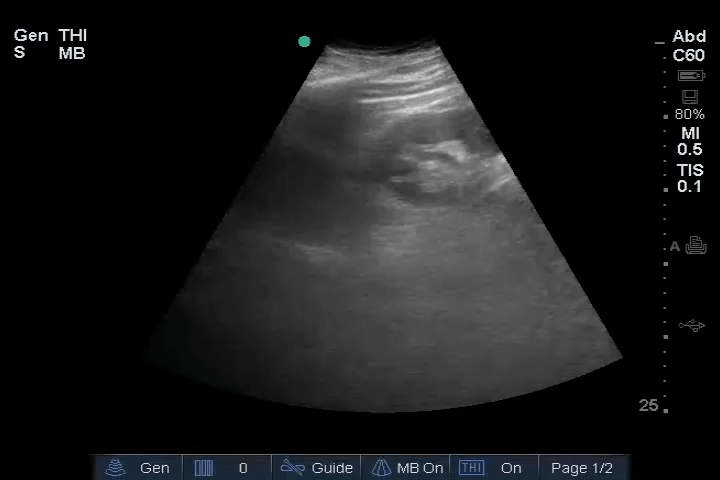

20_Abdomen_RUQ_Perihepatic (normal)

22_Abdomen_LUQ_Perisplenic (normal)

23_Abdomen_Pelvic_Sagittal (normal)

24_Abdomen_Pelvic_Transverse (normal)

25_Abdomen_Aorta_Transverse (normal)